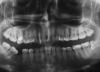

mayomy Опубликовано 28 сентября, 2007 Поделиться Опубликовано 28 сентября, 2007 Помогите пожалуйста советом! На 3-х передних верхних зубах стоят светоотверждаемые пломбы, зубы ими частично восстановлены лет 8 назад. 2 из них депульпированы, со временем пожелтели. Сегодня раскололась верхняя двойка, отлетел кусок пломбы, оголилось место ее примыкания к зубу. Самого зуба у меня половинка или даже меньше. Потемнение типа кариеса обнаружилось практически под десной. На соседних зубах тоже нужно менять все. Не знаю куда мне еще обратиться, у меня в городе(Ростов-на-Дону) нет знакомых или кем-то рекомендованнных специалистов. Боюсь что не смогу отличить хорошего от непрофессионала. У меня неправильный прикус, глубокий, дистальный кажется. Хотелось бы в перспективе его исправить, хотя мне уже 32 года. Кроме этого имеется пародонтит и хронический рецедивирующий стоматит (уже лет 17, не лечиться ничем, кроме поддержания иммунной системы). С этим стоматитом я так намучилась, гигиену соблюдаю. Боюсь протезирования из-за травмирования десен, они у меня плохо заживают, шрамы образуются. С отколотым зубом нужно что-то срочно делать! Соседние два тоже требуют ремонта, на одном из них две пломбы, на другом трещины эмали сильные еще со времени реставрации. Что можно сделать кроме протезирования? Если ничего, то чем протезировать? Можно ли будет потом исправить прикус? Прилагаю фото, лучше снять не позволяет техника. Спасибо. Ссылка на комментарий

mayomy Опубликовано 29 сентября, 2007 Автор Поделиться Опубликовано 29 сентября, 2007 Чтобы протезироваться Вам нужно разбираться сразу и с боковыми отделами. Делать отдельно передние зубы при отсутствии боковых (лежачие не в счет) и плохом прикусе - неграмотно, Вы эти коронки все равно либо расколете, либо выбьете. Пока можно восстановить композитом, чтобы дырку закрыть и искать хорошего протезиста, чтобы все сделать комплексно. Спасибо! Здравствуйте! Боковые пломбированы, пломбы так же нужно менять, чем заменить тоже незнаю. Лежачие -это 8-ки или нижняя 7-ка, которая "легла" из-за отсутствия (уже лет 15 прошло) 6-ки? Снимку года 1,5, сейчас десна 5-го зуба периодически воспалена, шейка сильно оголилась, наверное десна (а может и кость) "ушла" опять же из-за отсутствия зуба. Как его восстановить тоже не знаю, имплантанты нельзя, протез на 5-ку с парадонтитом тоже, 7-ка лежит уже совсем. Это тоже проблема, которую не знаю как решить. А какими протезами луше протезоровать передние и боковые в моем случае? Не знаю как мой стоматит хронический будет себя вести, протезы и здоровым людям то натирают, то еще что. Страшно подумать сколько это будет стоить. Ссылка на комментарий

mayomy Опубликовано 3 октября, 2007 Автор Поделиться Опубликовано 3 октября, 2007 Здравствуйте! Посетила врача, в общении понравился, но профессионально доверия не внушил (кариеса заметил на 3 зуба меньше чем ортодонт в тот-же день и другое...) Но напрвил к ортодонту, для консультации в плане лечения , они сошлись во мнении что пока нужно восстановить композитом. На зубах трещины сильные, я боюсь расколяться при сверлении(врач, делавший эти зубы об этом предупреждала). А более щадящего метода для удаления старых пломб чем бор нет? Сделала новые снимки, наверное еще обращусь в раздел ортодонтии. Телерентгенограмма какая-то неудачная, но нашла у нас только в одном месте ее. Пожалуйста, посоветуйте что-то насчет передних зубов и если не трудно, прокомментируйте вообще ситуацию в целом. Восьмерку наверное надо удалить. А вообще лечить кучу зубов сказали. Имеется нижняя шестерка жевательная, еще живая, но с 3-мя пломбами, требующими замены, думаю зуб придется убить, как его лучше восстановить? У нас всем штифты ставят, а я почитав тут, поняла что лучше вкладку и коронку(из чего?) Посоветуйте, пожалуйста, по всем вопросам, извелась я уже совсем. Зубы то-новые не вырастут, оттого велик страх совершить ошибку. А я такая, не могу решиться какой кефир в магазине купить из трех, и купить ли вообще, а тут зубы... Ссылка на комментарий